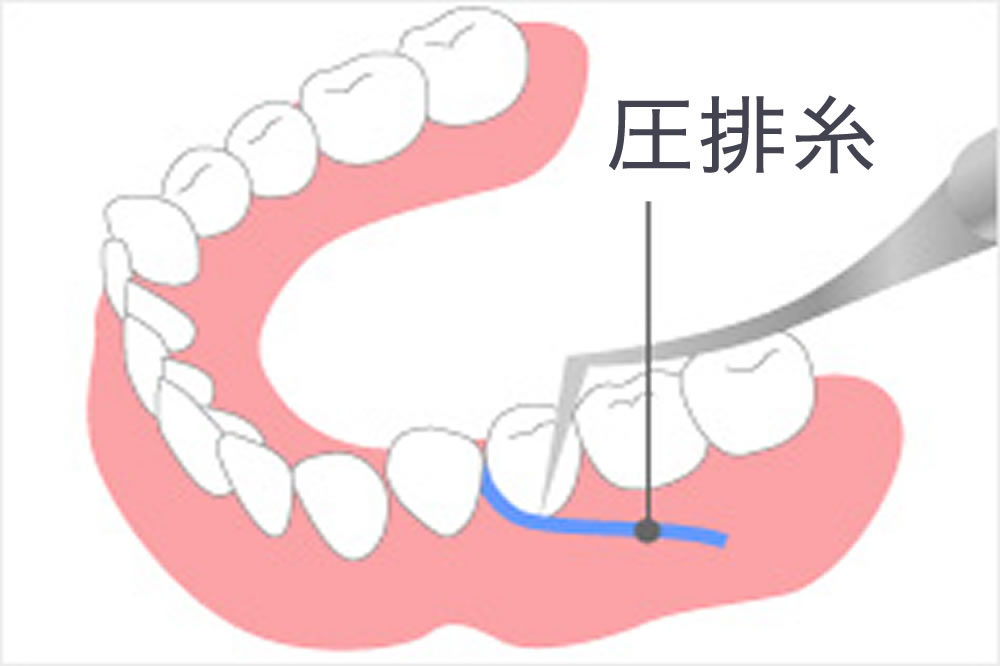

適合性の高さを左右する歯肉圧排

被せ物の長期維持を可能にするためには、土台となる歯としっかりフィットする事が大切です。当院では適合性を高めるために歯肉圧排を行い、型取りをしています。歯肉圧排とは、歯と歯肉の間を糸で押し下げ歯肉に覆われてる歯を一時的に露出させる処置です。この処置を行なう事で歯肉縁下までしっかり型が取れて精度の高いかぶせ物が作製可能となります。

被せ物の長期維持を可能にするためには、土台となる歯としっかりフィットする事が大切です。当院では適合性を高めるために歯肉圧排を行い、型取りをしています。歯肉圧排とは、歯と歯肉の間を糸で押し下げ歯肉に覆われてる歯を一時的に露出させる処置です。この処置を行なう事で歯肉縁下までしっかり型が取れて精度の高いかぶせ物が作製可能となります。